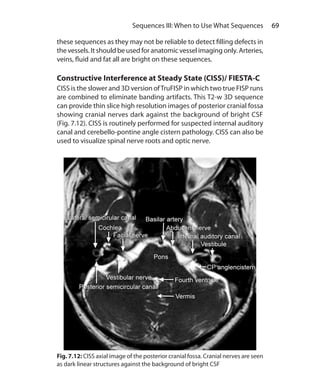

Assistant Professor